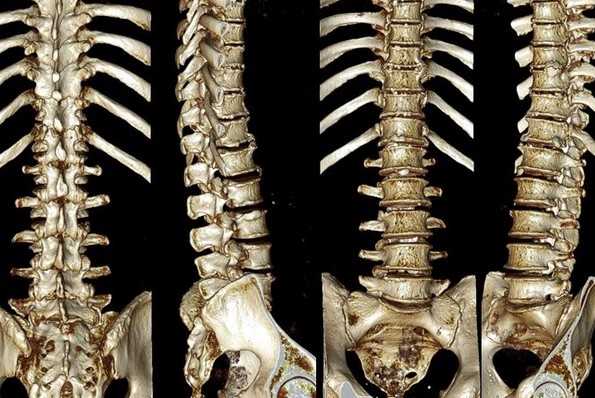

Перелом грудного отдела (трехмерная и сагиттальная проекции)

В результате компьютерной томографии получают серию послойных изображений рассматриваемой зоны. Монохромные фотографии обладают высоким разрешением. В отличие от рентгенографии на снимках отсутствуют дефекты и тени от расположенных рядом структур. Изменение плоскости при реконструкции изображений позволяет тщательно изучить анатомические образования. Преимуществом КТ является возможность создания 3D-модели позвоночника.

Трехмерная реконструкция при КТ

Отличия МРТ от КТ позвоночника

Основные отличия МРТ от КТ позвоночника кроются в принципе получения изображения. Современная компьютерная томография (или МСКТ - мультиспиральная компьютерная томография) основана на способности по-разному, в зависимости от плотности тканей, поглощать рентгеновское излучение. Особенности мультиспиральной компьютерной томографии позвоночника заключаются в том, что в ходе процедуры собираются множественные непрерывно перекрывающиеся срезы. Это дает возможность производить компьютерную обработку данных с последующим созданием объемных, так называемых 3D изображений и реконструкций. Полученные на МСКТ позвоночника снимки врачи могут рассматривать на экране с любой стороны как в режиме индивидуального просмотра, так и в режиме анимации, когда объект вращается вокруг своих осей. Используя специальные функции разворота и обрезки, можно выделить интересующую область и визуализировать ее с любой стороны. Это дает возможность медикам видеть скрытые структурные повреждения.